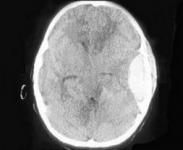

• 硬腦膜外膿腫

628健康網(wǎng)為您分享有關(guān)硬腦膜外膿腫的癥狀,硬腦膜外膿腫的治療方法,硬腦膜外膿腫的預(yù)防知識,硬腦膜外膿腫的癥狀圖片,硬...